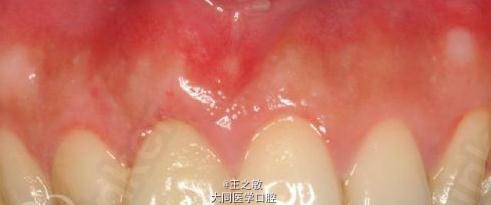

牙根裸露牙龈不齐

行牙龈移植术 处理:信封法撑开,根向深度5毫米,腭侧取结缔组织移植,把结缔组织当成信纸放入,使用可吸收线在近远中两侧做褥式缝合固定

治疗后三个月並以全瓷冠修复完成